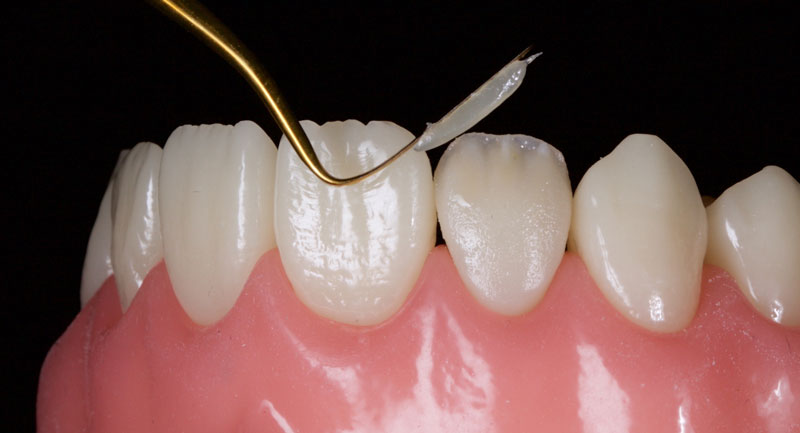

Finally, the incisal third is overlaid facially with a highly translucent enamel shade, e.g., WE Tokuyama (Fig. 14). This is smoothed and adapted with a No. 3 artist’s brush and a wetting resin.

The entire restoration is then covered with glycerin and polymerized with a curing light for 40s per surface to remove the oxygen-inhibited layer.